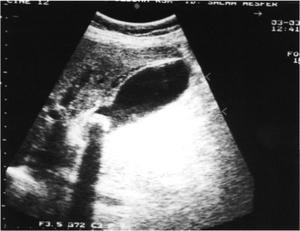

- Biliary ultrasound

- Gallstones

- Distinguish by characteristic "shadowing"

- GB wall thickening (>3mm)

- Pericholecystic fluid

- Sonographic Murphy's Sign (PPV 92%)

- CT

- Useful when ultrasound results are equivocal